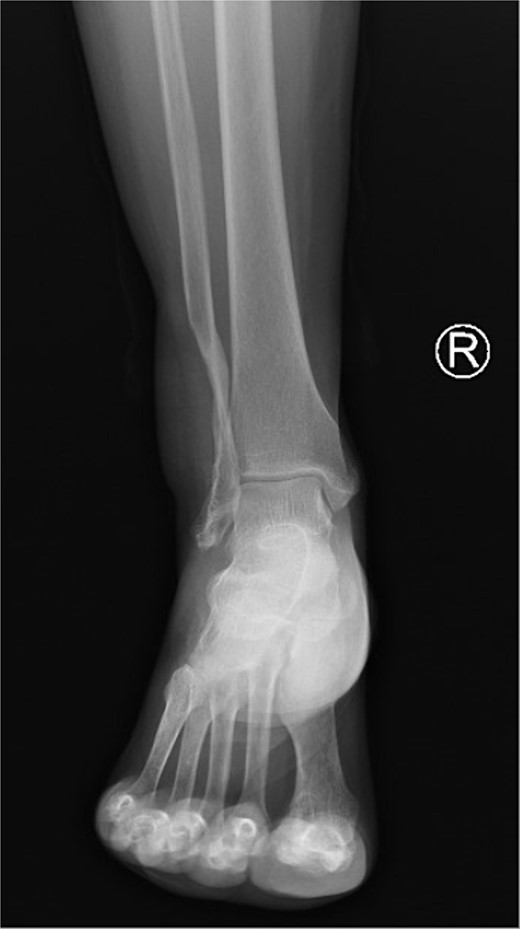

On imaging, an ankle X-ray showed an oval soft tissue mass subcutaneously at the level of the distal fibula (Fig. 2). The MRI showed about 5.7 × 3 × 5 cm of well-defined soft tissue mass within the distal lateral compartment of the lower leg, which seems locally invasive, abutting the fibular cortex, but without evidence of fibular cortical invasion (Supplementary Fig. 1). Moreover, a whole-body CT confirmed the absence of metastasis. CRP, ESR, LFT, and KFT were all within the normal range, and her bone profile was normal for her age. However, hemoglobin levels were slightly decreased (10.5 g/dl). An incisional biopsy showed features consistent with UPS. Therefore, the decision was to proceed with wide tumor resection and radiotherapy sessions.

The patient started having regular follow-up visits 1 week after the procedure, in which at the last follow-up she had a well-healed wound, showed no scar abnormalities, and had a mildly elevated thickness compared to the surroundings (Fig. 5). The patient had paresthesia in a small area at the posterolateral aspect of the ankle under the lateral malleolus. However, there were no limitations on movement, and the patient was able to bear weight and comfortably wear shoes. Moreover, a follow-up X-ray showed no abnormalities (Fig. 6).